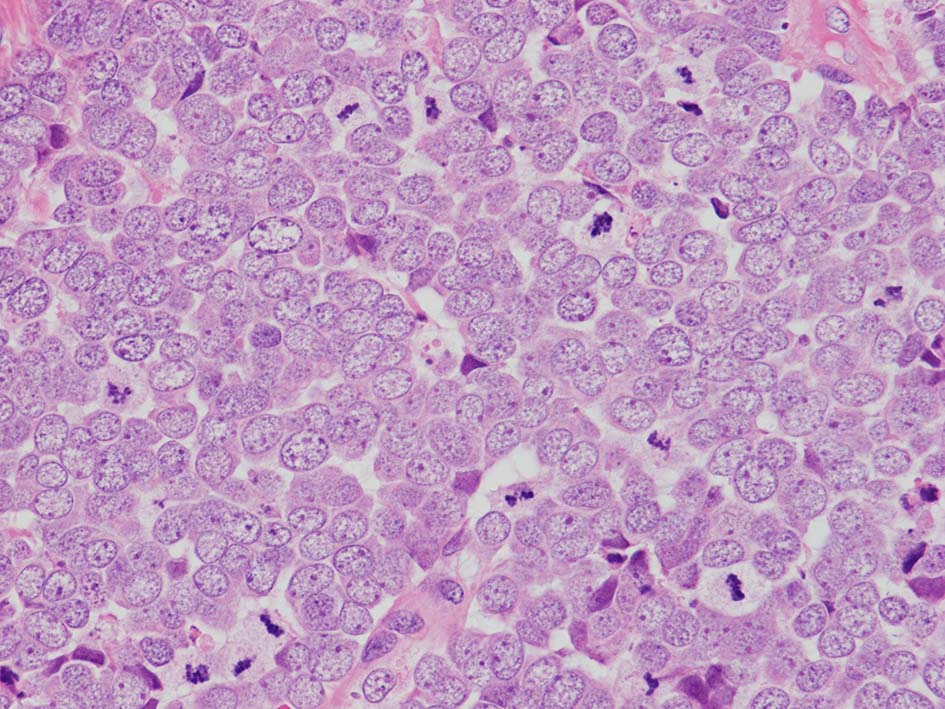

典型的な腫瘍細胞は円形, 卵円形の比較的均一な形態で「salt-and-pepper」と称される微細顆粒状クロマチンを有する小型円形核をもつ. MCPyV陽性例が均一な小型円形核を呈する傾向があり, 陰性例では, 核多形性が目立つととする報告がある.

- trabecular typeは円形から多稜形の腫瘍細胞が索状に配列, 3形のなかで腫瘍細胞がもっとも大きく, 円形核と比較的豊富な細胞質をもつ.

- small cell typeは濃いクロマチン, 多形性を示す核をもつN/C比大の小型腫瘍細胞がびまん性に増殖する.

- intermediate typeではtrabecular, samll cell typeの中間の腫瘍細胞サイズを示す. 組織型としてはもっとも多い.

血管を間質にしてround cellsが索状に増殖する所見. rossett様配列がある. CK20は特徴的な dot-like patternを示す. クリックで大きな画像が見られます.